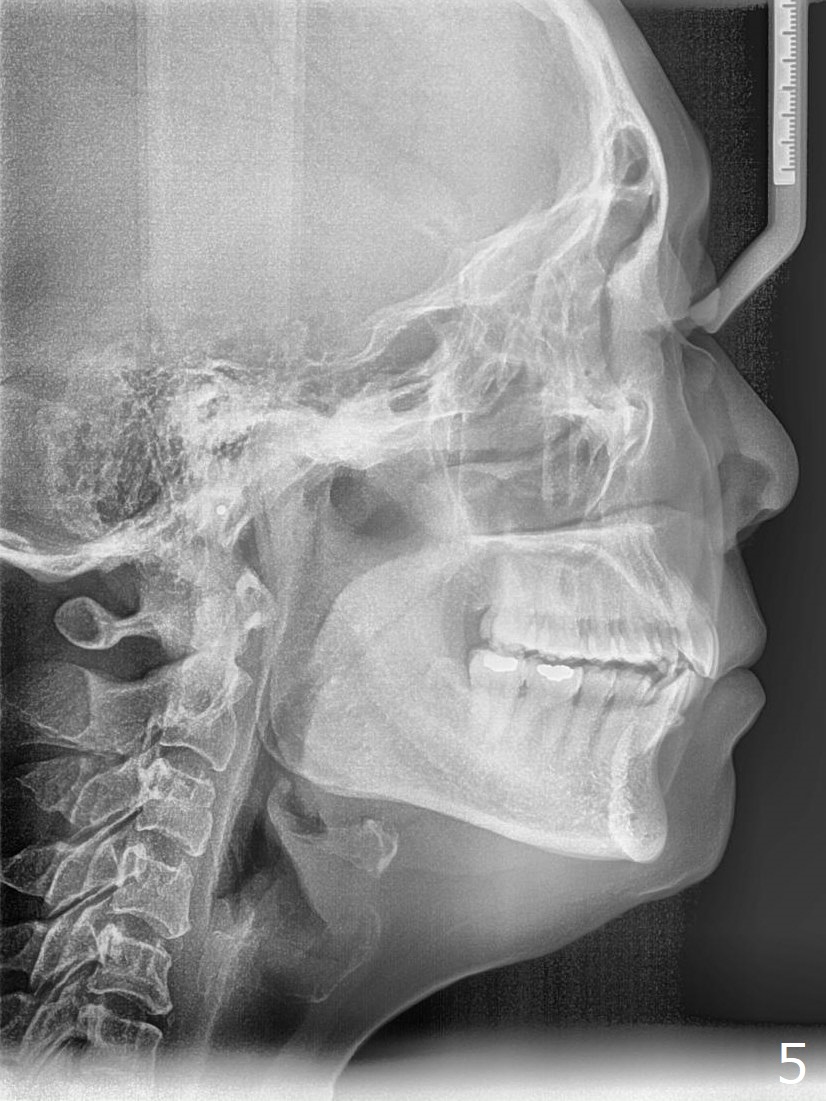

A 54-year-old woman (dento-phobic) will return for banding and bracketing 1.5 months post UR2 extraction with socket preser-vation. Lip strain is absent or minimal(Fig.1). The upper dental midline deviates to the right (Fig.2). Profile is within normal limit (Fig.3). UR3 is in cross bite (Fig.4). Cephalmetric X-ray apparently shows normal profile (Fig.5). Occlusion appears to be Class II in canine and molar (Fig.7,9, Class II Division II Malocclusion). The upper and lower dental midlines mismatch (Fig.8). UL2 is a peg lateral (Fig.10), while the lower anteriors are crowded (Fig.11). Arch wire sequence is conducted and let the timid patient decide whether the 2nd part of treatment should restore ideal occlusion with UR2 implant and UL2 veneer or simply close diastemata. Take PAs for the anteriors prior to banding to follow up root resorption during treatment.